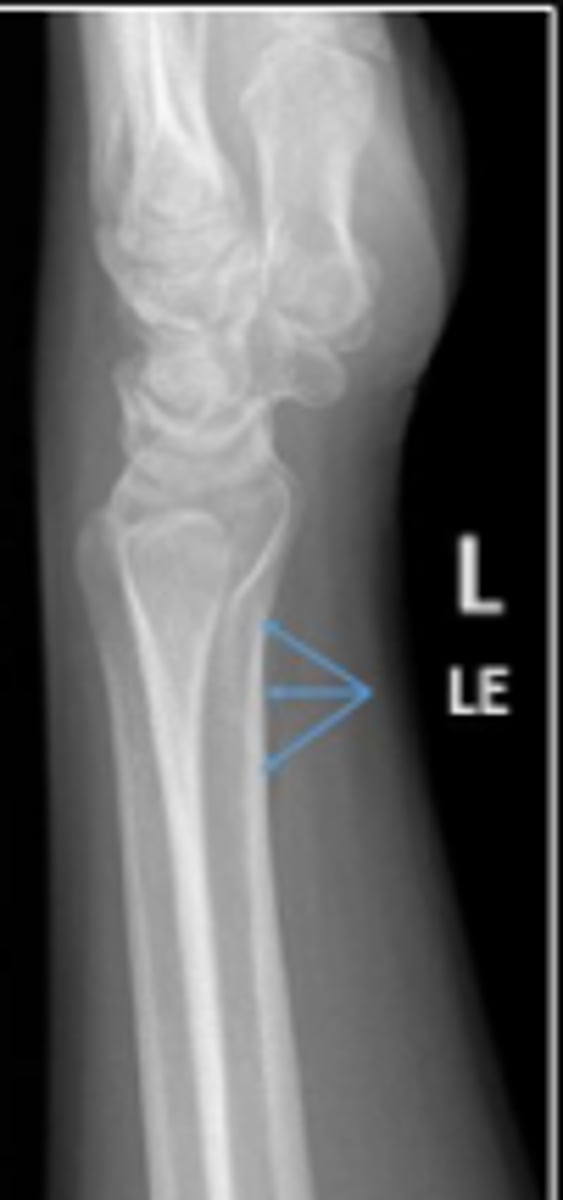

Left lateral wrist

What is the name of the radiographic view?

DRUJ

What is the arrow pointing to?

< and equal to 2mm

What is the normal measurement of this space?